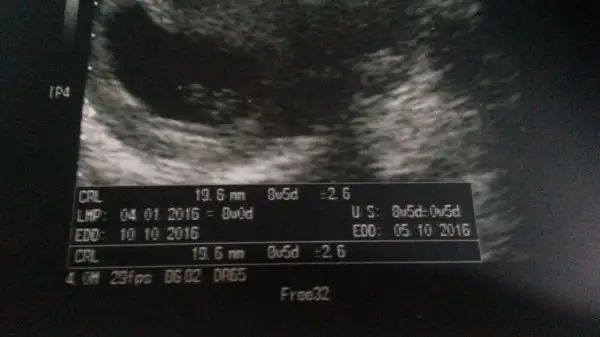

birde buraya yükliyeyim :) sata göre 10+4 usg ye göre 11+1 alttan muayene